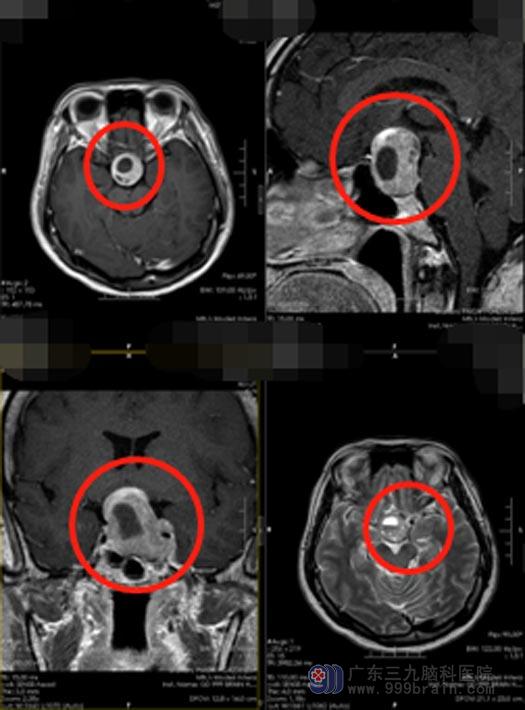

为寻求进一步的诊治,陈女士来到了广东三九脑科医院神经外五科,诊断为“鞍区占位:考虑垂体大腺瘤”。由于视神经位于大脑的鞍区,与垂体相邻,随着肿瘤的长大,常常容易对视神经、视交叉造成压迫,从而造成视力下降、视野缺损等症状。陈女士的磁共振检查结果提示肿瘤大小约3.5cm×2.5cm×3.5cm,由于受到肿瘤的压迫,视交叉在磁共振影像上已经看不清了。